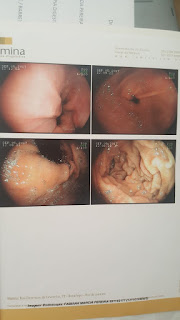

Vou

postar abaixo as imagens e laudos dos exames para que vocês possam ver com os

próprios olhos.

3 meses, fui fazer minha endoscopia de rotina e lá continuava ele (barret) e

mais algumas alterações como gastrite. Enfim... tudo na mesma como já era de se

esperar.

1 mês após, fiz a nova endoscopia. Meu marido que é médico me acompanhou e

esteve presente durante todo o exame.

Resultado:

não foi encontrado nada de errado com meu esôfago e nem com o meu estômago. O

Barret simplesmente desapareceu junto com a gastrite.